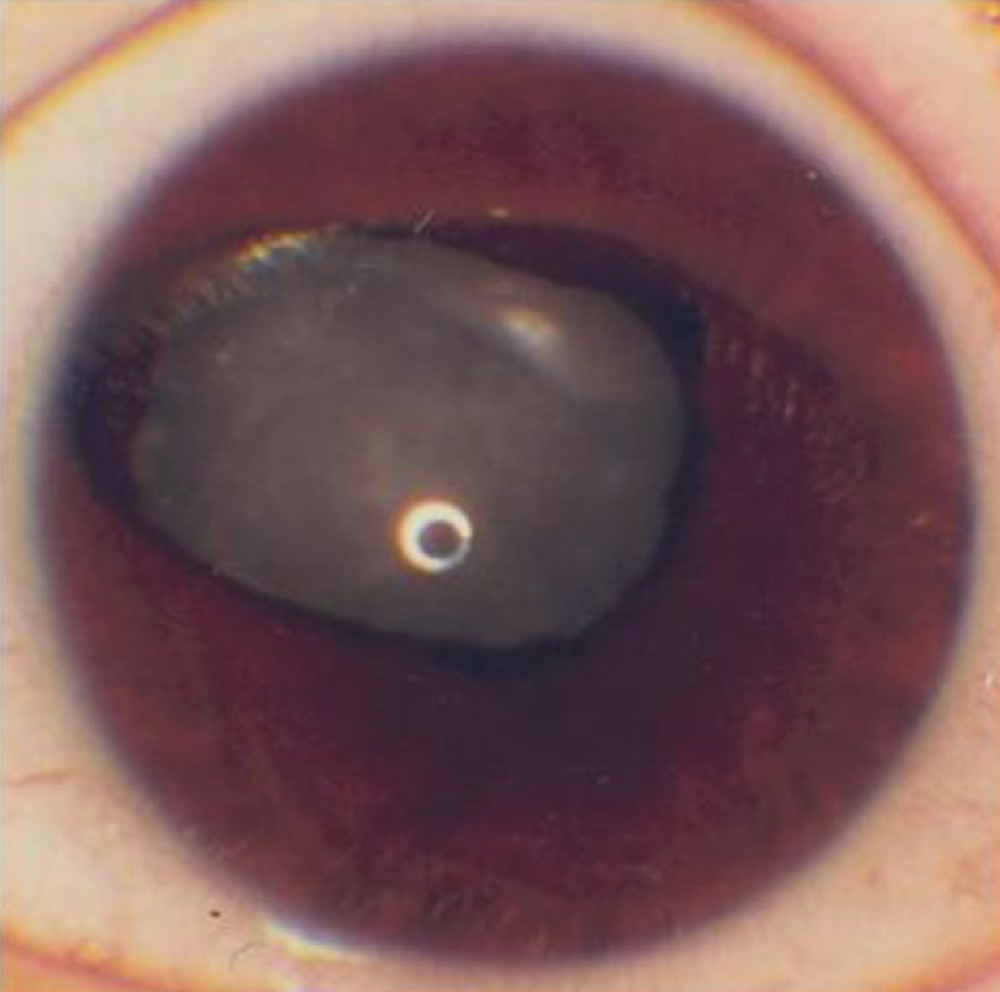

Figure 2. Left eye iris of aniridia case 6

who had a novel missense mutation (c.361T>C) located in the NH2-region

of the paired domain of PAX6. This eye exhibited partial

absence of iris, an atypical sector nasal iris coloboma (Iris 4),

stromal hypoplasia, and a total cataract.